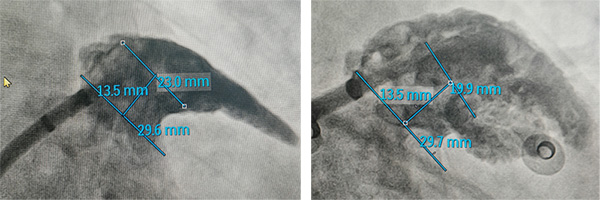

再次测量:更换封堵方案,再次测量心耳的锚定区为20-23mm,封堵区为29mm,综合选择2436LAmbre进行封堵。

植入过程:通过渐进式植入固定盘,在右肩位及肝位确定固定盘抵达预定位置且完全展开。